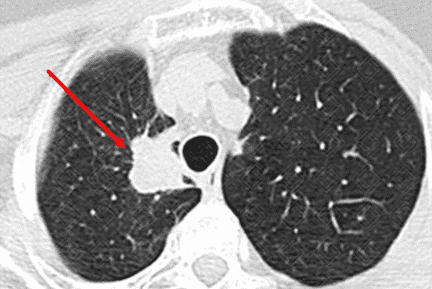

Descrição das figuras 1, 2, 3 e 4: Tomografia computadorizada do tórax, seguida de reconstruções axiais e sagitais. Massa pulmonar, com contornos espiculados, localizada no segmento apical do lobo superior direito, medindo 3,2 cm x 1,5 cm x 2,2 cm (setas vermelhas).

Lembrando que, acima de 3 cm, a lesão já deve ser descrita como massa. Lesões menores que 3 cm são descritas como nódulos. Isso também é importante no estadiamento TNM (lesões ≥ 3 cm já são consideradas pelo estadiamento como T2).